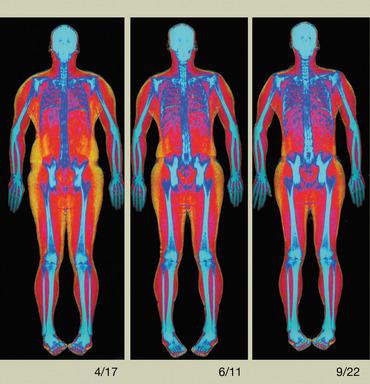

- Advanced Body Composition assessment with visceral fat estimation to assist in the evaluation of metabolic health.